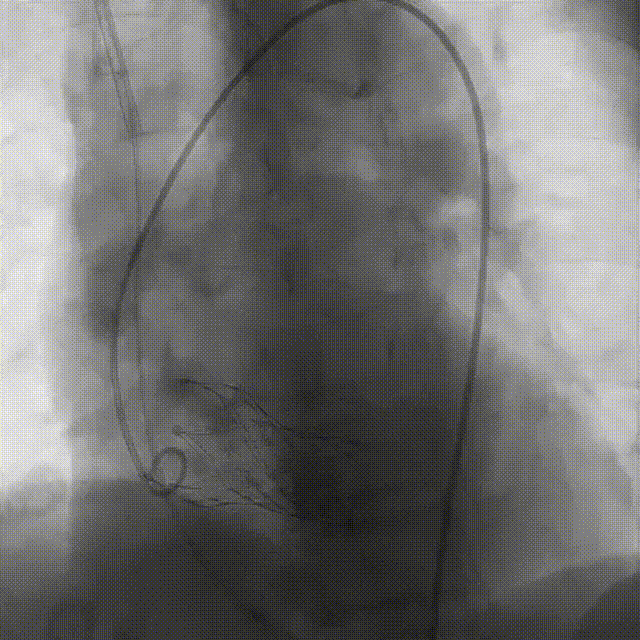

刘煜昊教授 阜外华中心血管病医院(点击查看专家详细简历) 首瓣选耐久,干瓣护航全生命周期管理 2025年ESC专家共识里指出:“推荐第一个瓣膜要选经证实具有长期耐用性的外科瓣膜与经导管瓣膜,以降低再次介入治疗的可能性 ,对于瓣环较小、根据预测有效瓣口面积(EOA)评估存在严重 PPM 风险的患者,可采用主动脉根部扩大术联合 SAVR,或植入环上瓣,对于小瓣环患者自展瓣拥有比较好的血流动力学优势”。 每一次术前评估,都是我们与患者携手面对未知的起点。我们始终以患者全生命周期获益为核心,在瓣膜选择与术式规划中,不只着眼于当下解剖适配,综合评估解剖条件、预期寿命与生活质量。从年轻患者到高龄人群,瓣膜耐久性与血流动力学稳定性始终是决策核心! 陈同峰教授 阜外华中心血管病医院(点击查看专家详细简历) 医学的进步正不断拓宽生命的边界,每一次术前评估都是对生命尊严的深度凝视,技术与人文的交融,让风险不再仅是数字的堆叠,而是成为医者与患者共同面对未知的勇气见证。术中瓣膜释放结束,到了导管测压的时候,我惊喜:瓣膜不错啊,压差为0,这不仅仅得益于瓣膜形态的设计,更是环上瓣及瓣叶材质优质的体现,感受到了 Prostyle A瓣膜在血流动力学上的卓越表现,其采用的抗钙化处理技术有效延长了瓣膜的耐久性,为患者长期生存提供了更可靠的保障。 患者病史 主诉:心慌半月; 门急诊诊断:心悸,冠状动脉粥样硬化性心脏病,心脏瓣膜病,主动脉瓣狭窄,高血压,甲状腺术后; 现病史:半月前无明显诱因出现心慌,呈间断性,伴心悸、出汗,伴头晕,无咳嗽、咳痰,无恶心、呕吐,无双下肢水肿,无放射痛及意识障碍,休息约几分钟后可自行缓解,症状反复发作,遂来我院就诊。 术前超声提示:室间隔增厚;主动脉瓣退行性变并重度狭窄;升主动脉明显增宽;室间隔增厚。 术前CT 三叶瓣,轻度钙化集中在无窦和左窦瓣叶边缘,主动脉根部直径19.3mm,LVOT直径17.7mm,LVOT向下收窄; 窦部正常,VTC空间足够,冠脉风险低; 左室腔小,收缩末径20-25mm,“自杀左室”,循环崩溃风险高;主动脉瓣环水平夹角71.1°,横位心,过弓和跨瓣存在一定困难,备snare。 外周双侧入路内径可,双侧入路能够支持20F大鞘通过,右股低分叉。 手术策略 推荐右侧股动脉为主入路,左侧为辅助入路,右股分叉上方1cm穿刺;推荐选择AV23瓣膜,18mm球囊预扩,左右重叠位:LAO 7° CAU 35°;左冠切线位:LAO 27° CRA 16°;右窦居中位:LAO 18° CAU 9°;备Snare,建议ECMO/CPB湿备,术前术中积极补液,警惕循环崩溃风险。 手术过程 在右股动脉穿刺建立通路后,顺利送入大鞘,经食道超声及血管造影确认路径稳定。18mm球囊预扩过程中,患者血压一度下降,迅速完成扩张并立即植入AV23 ProStyle A®瓣膜。瓣膜精准释放于目标位置,超声显示无明显反流及瓣周漏,血流动力学即刻改善。 主动脉根部造影 18mm球囊预扩少量反流 输送系统柔顺跨瓣 精准定位 平稳释放 80%工作位观索位置合适 释放后导管测压,压差由术前53mmHg降为0mmHg 最终造影瓣膜位置形态良好,冠脉灌注良好,无明显瓣周漏 ProStyle A®预装干瓣——助力临床最优化解决方案: 轻松过弓,精准可控:该病例为横位心,在未使用snare的情况下,过弓和跨瓣柔顺,较细的尺寸+柔顺的输送系统通过性能得到了很好的验证; 平衡的收腰设计:该病例瓣环较小且左室腔小,AV23瓣膜的平衡收腰设计既确保了锚定安全性,又保证了EOA,有效降低了循环崩溃风险,而术后0mmHg的压差的表现更加证明了优秀的血流动力学,提高了瓣膜的耐久性; 预装干瓣 便捷顺安:金仕生物专利抗钙化技术运用纳米技术去除组织内的细胞碎片和磷脂,封闭游离醛基,从根本上阻断了瓣膜钙化的多项因素,显著提升了瓣膜的耐久性;同时,相比较传统戊二醛保存方式,干式存储最大限度的保留心包的亲水亲油平衡,还原组织天然曲柔性,进一步保障了瓣叶开合,保证长期耐久性。 专家简介 王小虎 阜外华中心血管病医院(点击查看专家详细简历) 陈冲 阜外华中心血管病医院(点击查看专家详细简历) 赵一品 阜外华中心血管病医院(点击查看专家详细简历)